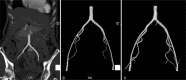

Results: The saddle embolism was removed completely. After 1-month follow-up, the computed tomography angiography (CTA) examination showed neither stenosis nor thrombus in the abdominal aorta and iliac artery. The patient achieved perfect outcome.